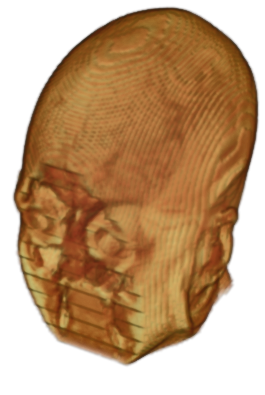

To prevent these types of attack, medical scans are currently de-identified using crude removal-based techniques [Bischoff-Grethe et al.(2007)Bischoff-Grethe, Ozyurt, Busa, Quinn, Fennema-Notestine, Clark, Morris, Bondi, Jernigan, Dale, Brown, and Fischl, Schimke et al.(2011)Schimke, Kuehler, and Hale, Milchenko and Marcus(2013)] which seek to remove privacy-sensitive parts of the head (examples in Figure 3). However, as we demonstrate, these existing techniques fail to reliably hide the patient’s identity – or they are so aggressive that they impair further medical analyses. A better solution is needed.

Benchmark De-Identification Methods. We compare our result with three publicly available and widely-established methods for de-identification of MRI head scans, depicted in Figure 3. All methods have in common that they (1) are not deep-learning-driven, (2) require no additional training and (3), are used on a day-to-day basis in neuroscience and clinical research. All procedures were applied with default settings on images of resolution . The methods include QUICKSHEAR [Schimke et al.(2011)Schimke, Kuehler, and Hale], FACE MASK [Milchenko and Marcus(2013)], and DEFACE [Bischoff-Grethe et al.(2007)Bischoff-Grethe, Ozyurt, Busa, Quinn, Fennema-Notestine, Clark, Morris, Bondi, Jernigan, Dale, Brown, and Fischl]. Descriptions of the methods are provided in the Appendix. We also include MRI WATERSHED [Ségonne et al.(2004)Ségonne, Dale, Busa, Glessner, Salat, Hahn, and Fischl], a skull-stripping method that removes everything except the brain.

A handful of de-identification techniques exist for MRI scans, which are conventionally used for sharing and distribution of MRI data. These existing methods rely on a removal approach to privacy. DEFACE [Bischoff-Grethe et al.(2007)Bischoff-Grethe, Ozyurt, Busa, Quinn, Fennema-Notestine, Clark, Morris, Bondi, Jernigan, Dale, Brown, and Fischl] estimates the probabilities of voxels belonging to the face based on an atlas of healthy control subjects. The scan is de-identified by setting intensities of voxels whose probabilities are small enough to zero. QUICKSHEAR [Schimke et al.(2011)Schimke, Kuehler, and Hale] is a fast but simple approach that computes a hyperplane to divide the MRI into two regions: one containing facial structures, and the other containing the brain of the scan. Voxels in the first part are set to zero. FACE MASK [Milchenko and Marcus(2013)] uses a filtering method to blur the facial features. These existing de-identification approaches are based on traditional computer vision techniques; we believe that the proposed algorithm is the first to adopt a learning-based approach.